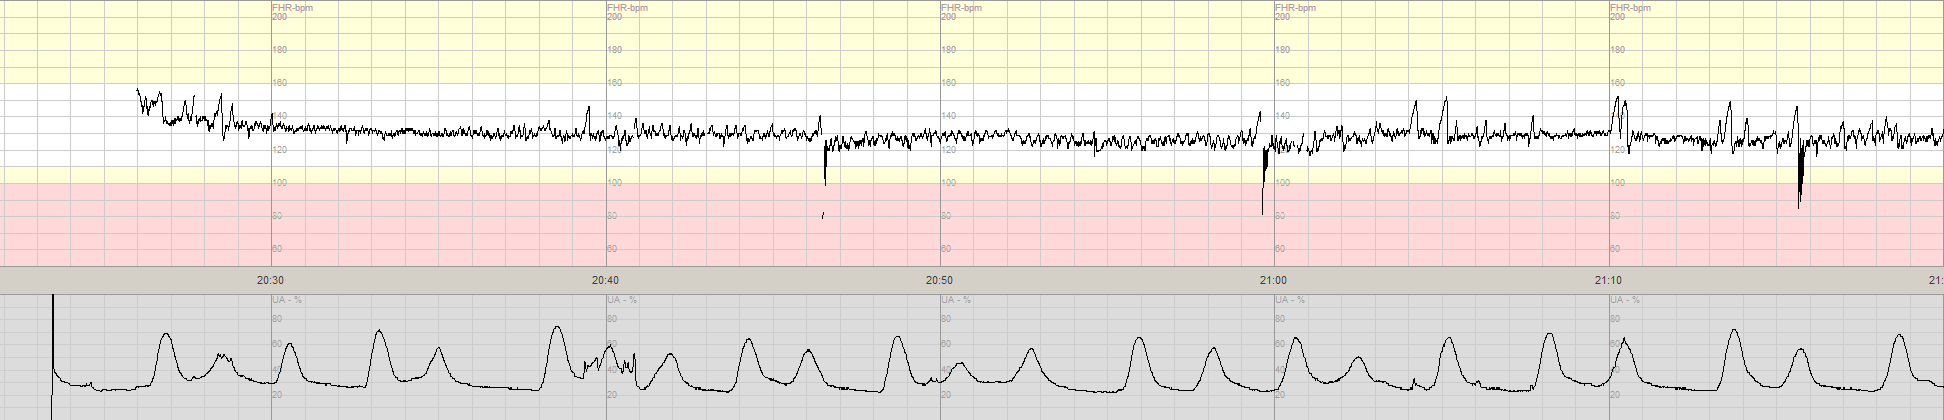

Här ett normalt CTG med god kvalitet.

Normalt CTG (intern registrering).